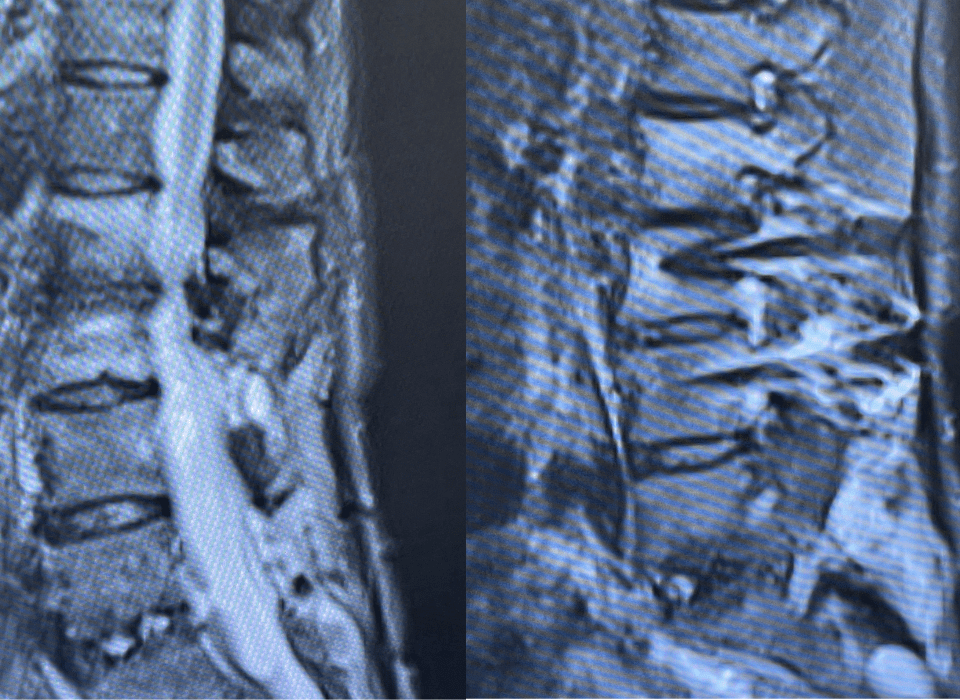

This 62-year-old female presents with chronic intractable low back pain with radiation down the front of her thighs. The patient had had two prior fusion surgeries: […]